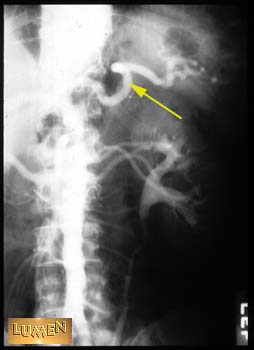

Question: Identify.

Splenic artery.